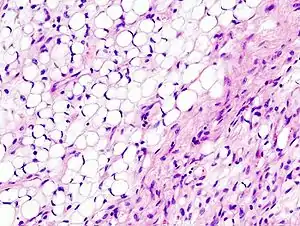

Pathology

Histopathologically, ALT/WDL tumors are divided into adipocytic/lipoma-like, sclerosing, and inflammatory variants with adipocyte/lipoma-like being the most common. Adipocytic/lipoma-like ALT/WDL tumors consist of lobules of mature fat cells variably intersected with irregular fibrous septa (see the adjacent H&E stained photomicrograph). Sclerosing ALT/WDL tumors, the second most common variant, develop primarily in the retroperitoneal and paratesticular areas; it consists of scattered, atypical stromal cells within a collagenous (i.e. collagen-containing) stromal tissue background. Rare vacuole-containing lipoblasts populate this tissue. Inflammatory ALT/WDL tumors are the rarest variant. they occur most frequently in the retroperitoneum and consists of chronic inflammatory cells, e.g. lymphocytes and plasma cells plus occasional lymph node-like follicles interspersed throughout a tissue background containing fat cells.[14]